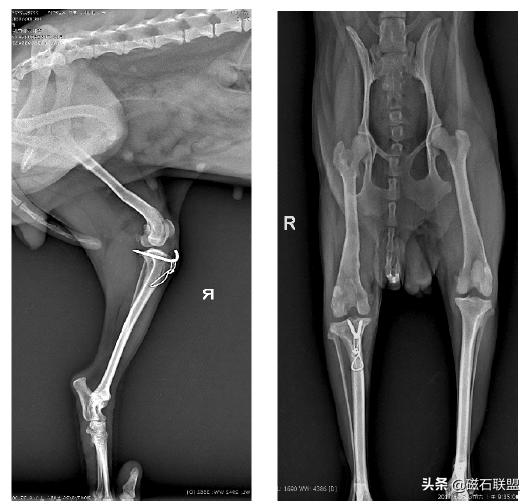

★手术方案:

对于滑车沟未变浅、胫骨及股骨未发生畸形者:可将脱位对侧的韧带重叠缝合,以紧缩关节囊,使髌骨复位。

对于滑车沟变浅者:应进行滑车再造成形术。对胫骨嵴生长内旋者,可将胫骨嵴移向外移动1 cm~2 cm,并用1 枚~2 枚骨针与手术钢丝固定。

★术后影像

★愈后:

手术后2小时即恢复清醒,一个月后基本恢复正常行走,取出钢针后恢复较为良好。